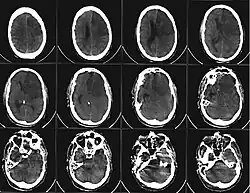

Craniale Computertomographie

Die craniale Computertomographie (cCT oder CCT) ist eine radiologische Untersuchungsmethode, mit der mittels scheibenartiger Schnittbilder vor allem das Gehirn, aber auch knöcherne Anteile, Gefäße, Gehirnkammern mit Hirnflüssigkeit sowie die übrigen Weichteile im Inneren des Schädels und jeweils viele pathologische Veränderungen dieser Strukturen visualisiert werden können. Es handelt sich dabei um ein bildgebendes Verfahren, das für die moderne Neurologie große Bedeutung hat.